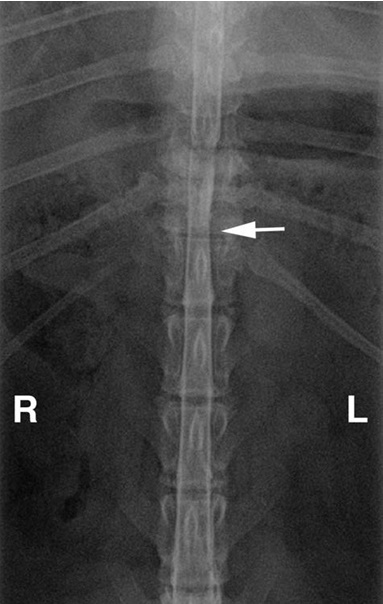

Μυελογραφία σε Pug σε κοιλιοραχιαία προβολή. Εμφανής συμπίεση του ΝΜ μεταξύ Θ11-Θ12.